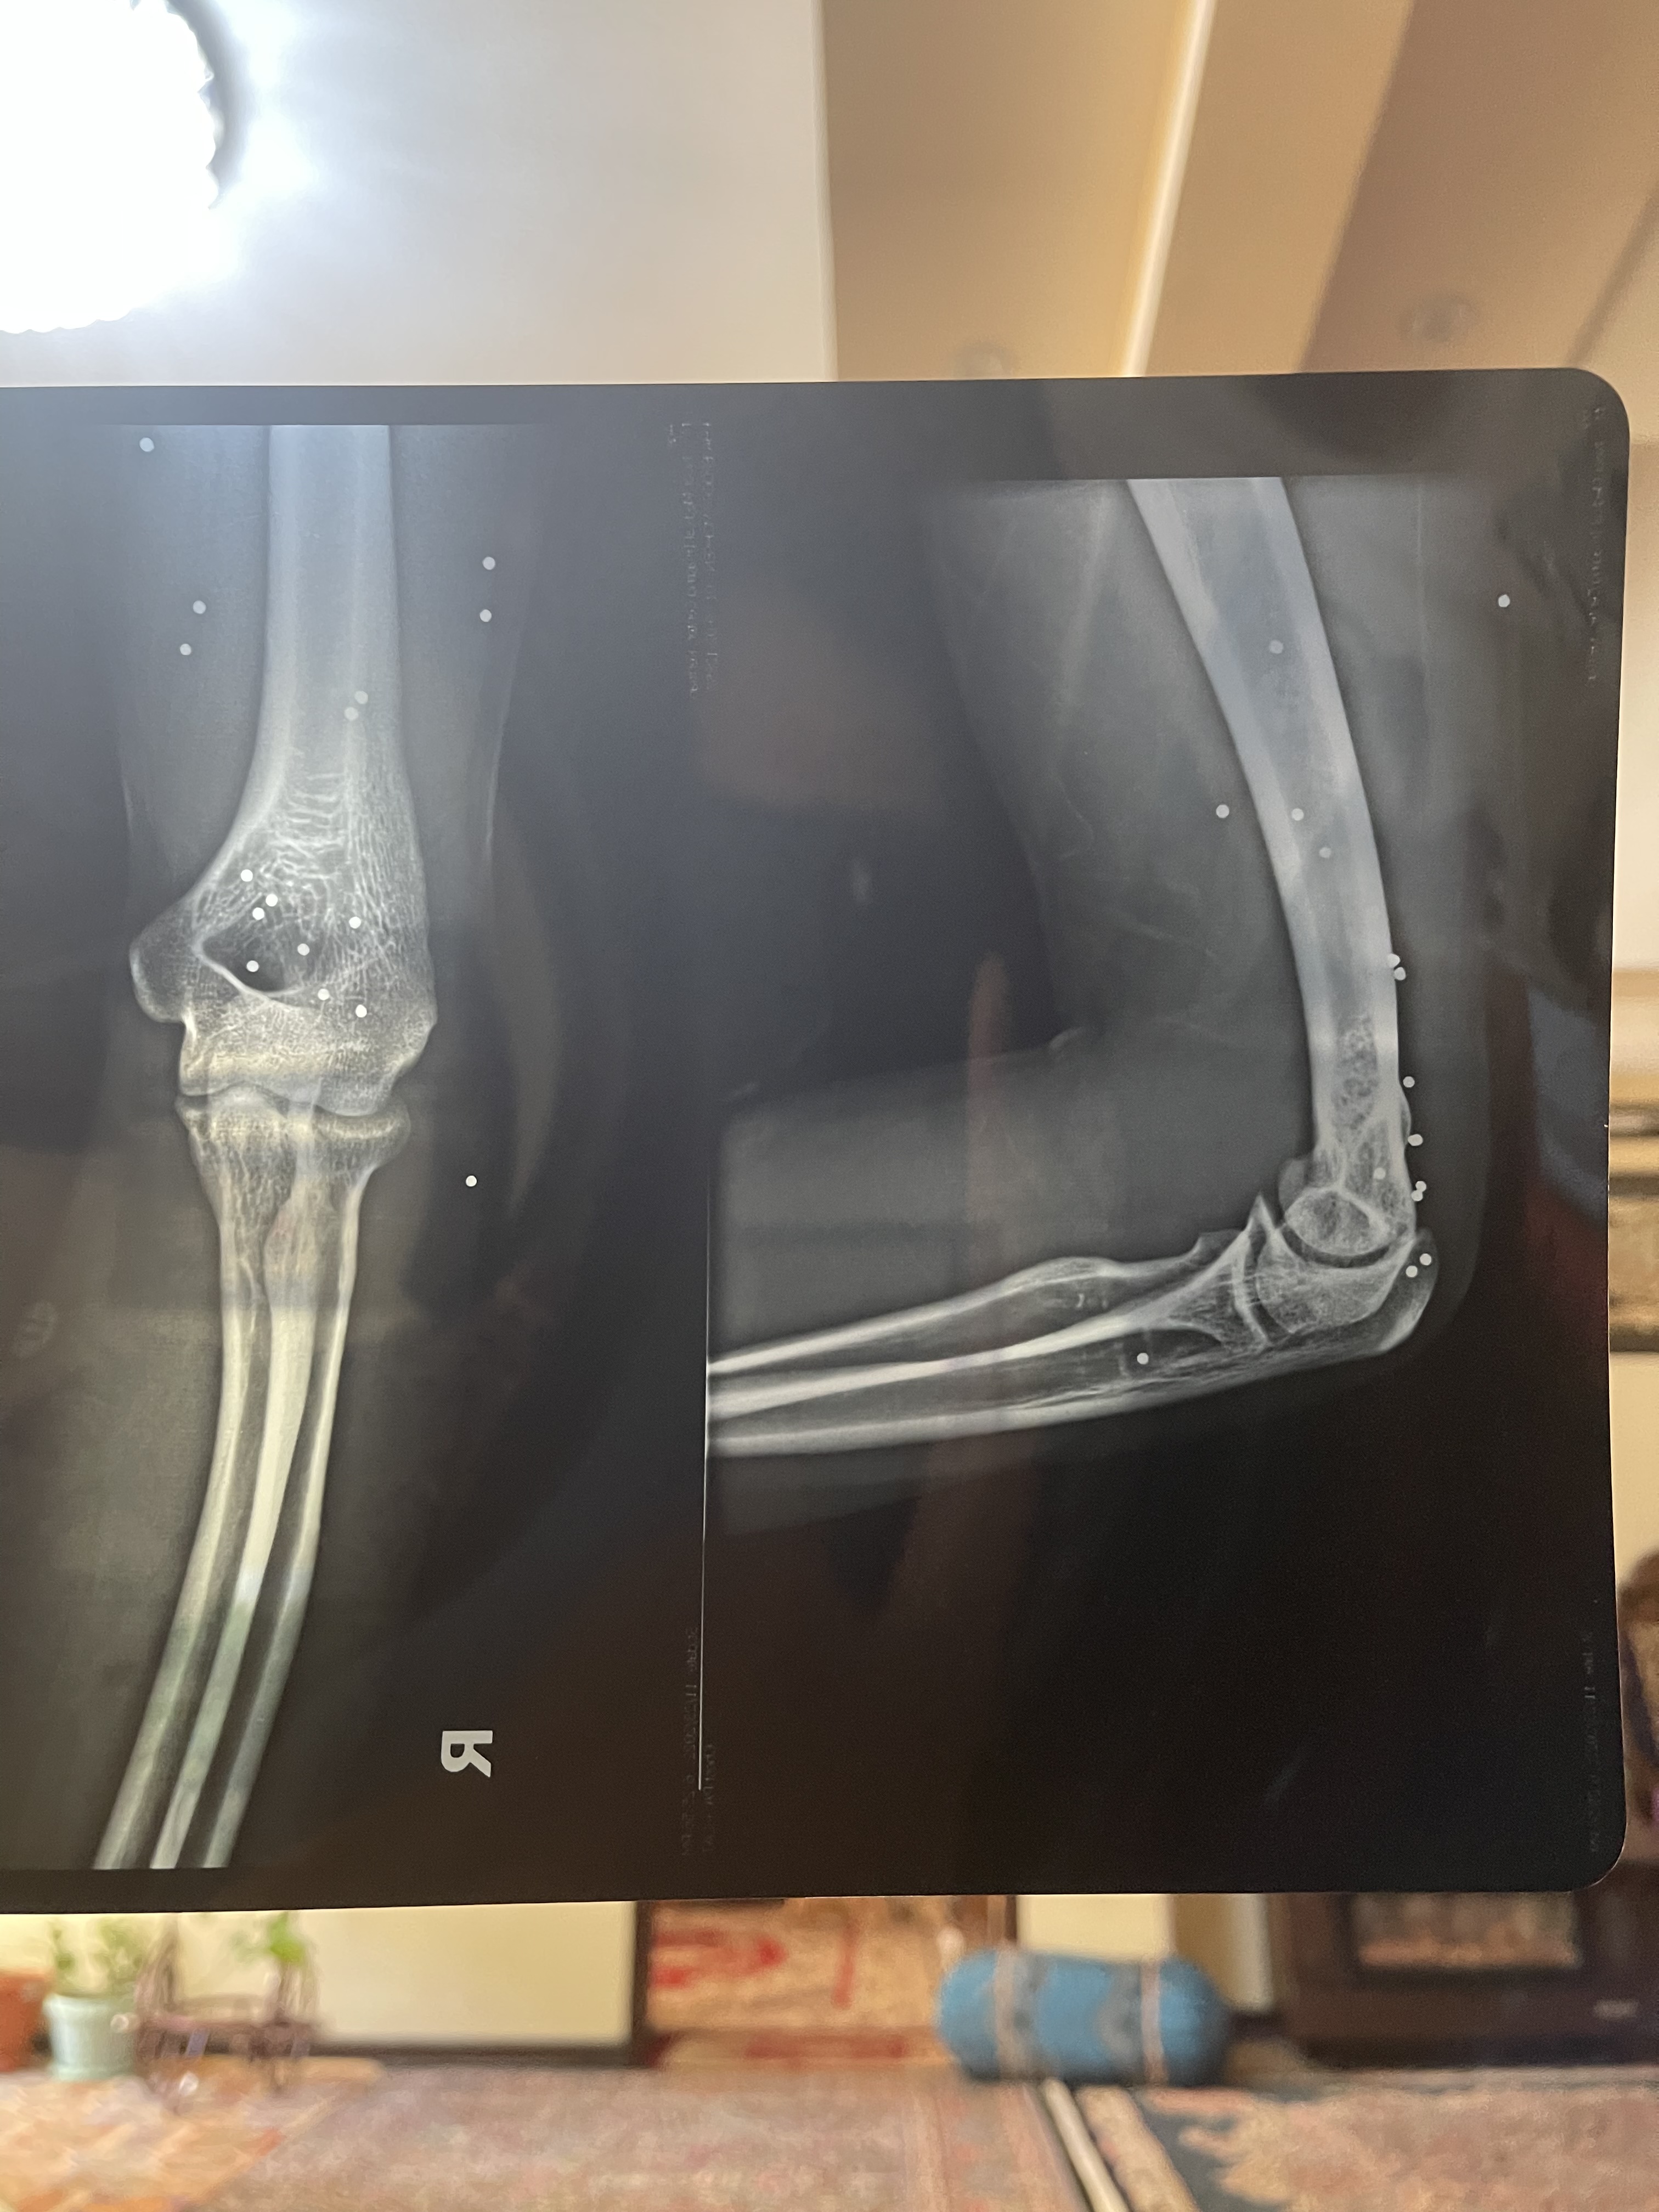

Hamid Reza was shot twice from a distance of about two meters with a pellet gun. One pellet goes right through his eye. Two pellets are implanted in his eye and his torso has so many that they’re difficult to count. In the immediate panic after being hit, Hamid Reza remembers screaming that he’s been blinded. He was holding his eyes shot in the shock. With the help of his friends, he managed to get to safety and they climbed into a car.

Hamid Reza was operated on that night and he left the hospital the next day for fear that it might to be safe to stay. He hasn’t sought follow up treatment for his eye which has no usable vision remaining. The rest of the pellets in his body, some were removed by a friend at Hamid Reza’s home. Eventually, they decided there were too many to try and remove them all.